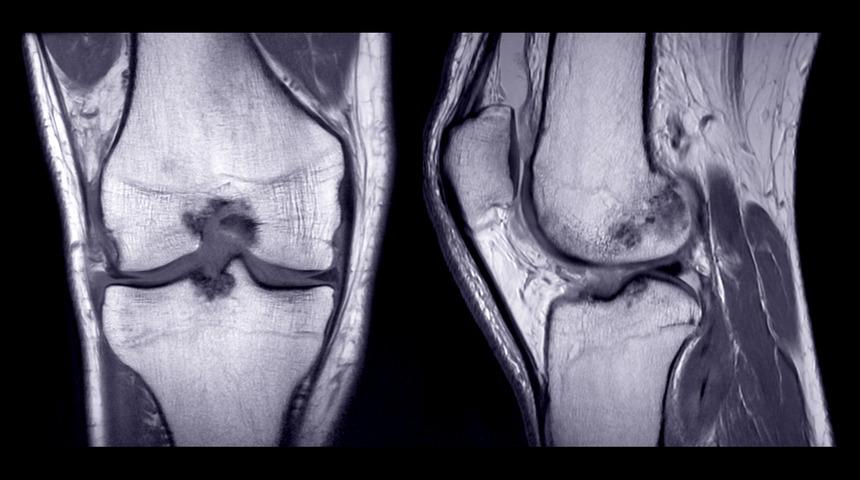

Uzun süreli koşanlarda kıkırdak hasarı daha fazla mı yaşanıyor?

UZUN SÜRELİ KOŞUCULARLA AŞINMA DAHA AZ

Bu noktada fazla spor yapmanın da bu sorunların ortaya çıkmasına neden olabileceğine dair yaygın kanıya dikkat çeken Yeditepe Üniversitesi Koşuyolu Hastanesi Ortopedi ve Travmatoloji Uzmanı Doç. Dr. Gökhan Meriç, 675 maraton koşucusunun 20 yıl boyunca takip edildiği bir çalışmada bunun tam tersinin ortaya konduğunu söyledi. Konuyla ilgili şunları anlattı: “Maraton koşucuları haftada 50 km’den fazla koşmasına karşın bu kişilerin diz ve kalça eklemlerinde kıkırdak aşınması yani kireçlenmenin normal insanlardan daha düşük olduğu gösterilmiştir, Koşma sırasında dizlere vücut ağırlığının sekiz katı kadar, kalçaya vücut ağırlığının beş katı kadar yük biner. Uzun süreli yüklenmeden dolayı kıkırdak hasarı gelişebileceği düşünülse de ancak maraton koşucularında veya uzun süreli koşan kişilerde gerçekten bu tip bir hasarlanmanın gelişmediği ortaya kondu.”

Bu sonucun nedenleri arasında maraton koşularının zayıf olmasına bağlandığını anlatan Doç. Dr. Gökhan Meriç, “Bu durumda her ne kadar yüklenme artsa da kilo fazlası olmadığı için yüklenmenin de çok ciddi oranda gerçekleşmemesi nedeniyle hasar yaşanmıyor” dedi. Çarpma darbe ve yüklenmenin çok daha fazla olabileceği futbol, güreş ağırlık kaldırma tenis gibi sporlarda tekrarlayan darbeye bağlı kıkırdakların, menüsküs ve bağlarda hasarlanmanın gelişebildiğinin gösterildiğini söyledi.